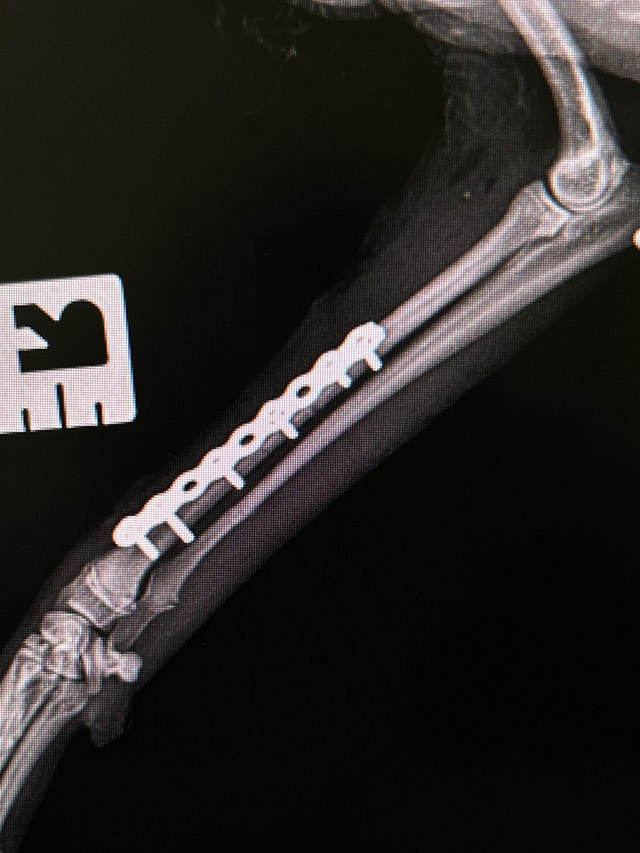

Osteosynteza

• Osteosynteza

Jest to zabieg polegający na stabilizacji złamania kości za pomocą implantów.